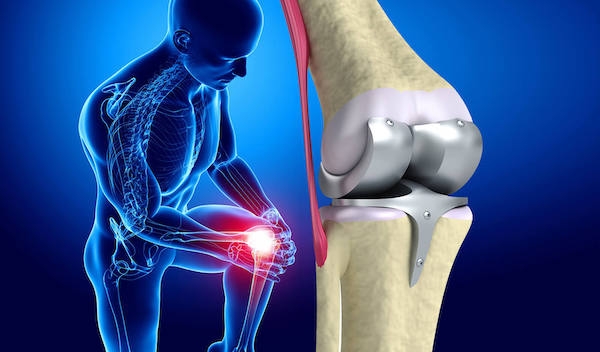

Cerrahi Tedavi Yöntemleri

Kireçlenme nedeniyle diz ekleminde ciddi harabiyeti olan ve günlük yaşamında ciddi aktivite sorunları yaşayan ileri evre diz kireçlenmesi hastaları cerrahi yöntemlerle tedavi edilir. Diz protezi ameliyatı, bu hastalarda ağrı ve işlevde önemli derecede iyileşme sağlayan başarı oranı yüksek bir tedavi yöntemidir.

Protez ameliyatları genel olarak; tam ( total) yada yarım (unikondiler) diz protezi olarak iki ana başlıkta değerlendirilebilir. Dizdeki kireçlenme eğer dizin iç yada dış bölümüne yada sadece diz kapağı altına sınırlı ise yarım diz protezi yapılabilir. Kireçlenmenin tüm dizde yaygın olduğu hastalarda ise total yani tüm eklemin değiştirildiği protezler uygundur.

Protez ameliyatı klasik teknikle yada robotik olarak uygulanmaktadır. Bazı cerrahlar, robotik ameliyatların başarı oranlarını artttırmadığını öne sürmekte ve gerekli olmadığını belirtmektedirler. Bazıları ise robotik cerrahiyi gelişmiş ve modern teknolojilerin uygulandığı cerrahi olarak tanımlamaktadır. Adı her ne kadar “robotik cerrahi” olsa da , ameliyat aslında, cerrahın protezin ve dolayısı ile yapay dizin açılarını doğru oluşturmak için diz kemik kesilerini bir robotik kol kullanarak yapılmasını içerir. Klasik diz protezinde bu işlem mekanik kılavuzlar yardımı ile yapılırken, robotik cerrahide açılar hastanın dizine ait anatomik verilerin cerrahi öncesinde robota yüklenmesi ve böylece daha doğru açılarda protezin yerleştirilmesi hedeflenir.

Robotik cerrahi özellikle, daha hassas ve teknik bir ameliyat olan yarım diz protezinde daha yüksek başarı sağlamaktadır. Tam diz protezine gelince, yeterince deneyimi olan cerrahlar, robotik cerrahi olmadan ve ameliyat süresi ve maliyetini arttırmadan başarılı sonuçlar almaktadırlar.